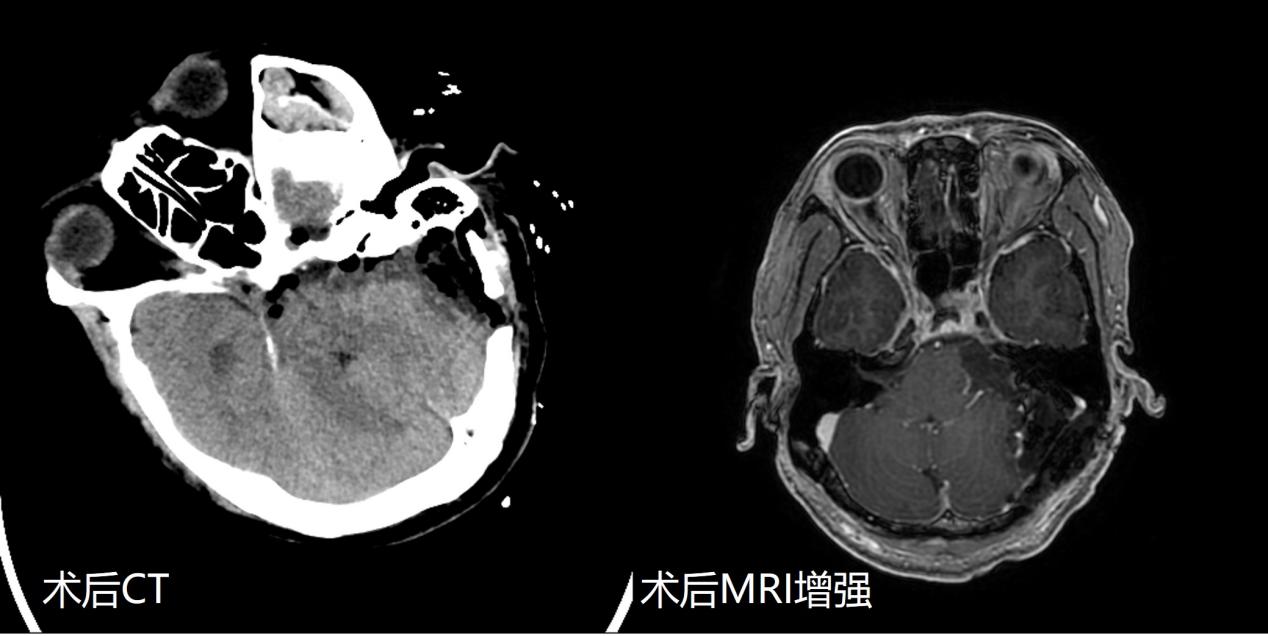

入院后,神经外科周乐教授、权俊杰副教授、马程文博士精心准备。在神经电生理监测技术辅助下,应用显微镜下神经束膜下分离技术,将肿瘤完全剥离切除,面听神经得到解剖保留。术后影像检查证实肿瘤完全切除。术后患者面部肌肉运动正常,同侧听力虽有下降,但仍有功能。目前患者已康复出院。

此次手术为医院首次听神经瘤全切+面神经保留+听神经保留手术,代表着二附院在听神经瘤手术领域达到国内先进水平。